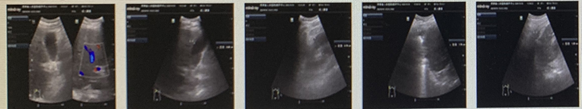

Figure 2 The result of Abdominal ultrasonography on November 9, 2020.

The abdominal ultrasonography was conducted on November 9, 2020. results showed that Gallbladder wall thickening, left renal cyst;the sonograms of liver, pancreas, spleen and right kidney were normal.